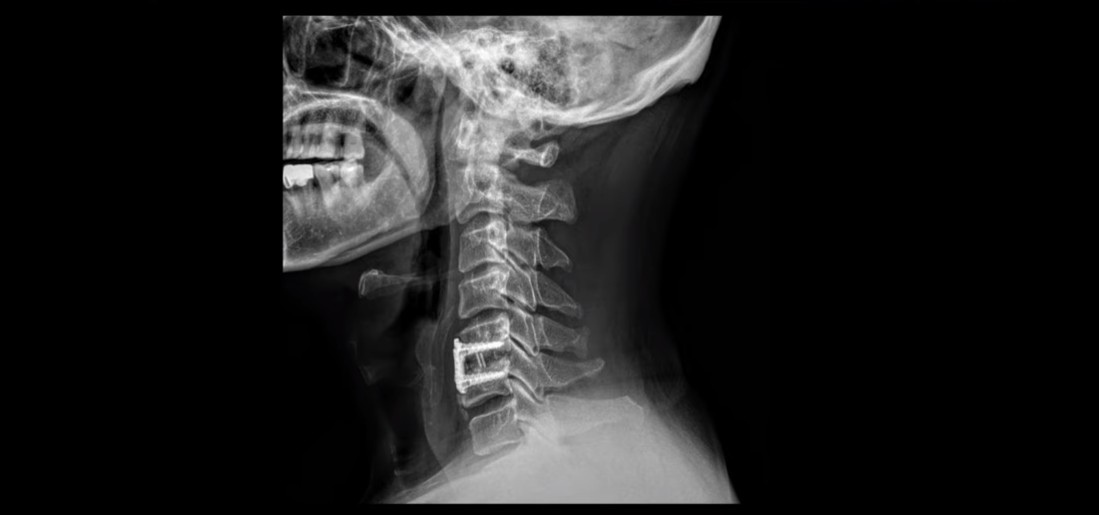

이분도 X-ray를 보면 완전한 일자목, 거북목 환자입니다.

이런 목의 형태를 가지고 있으면 만성적으로 목과 어깨가 아플 가능성이 높습니다. 앞으로 밀려나간 머리를 목 근육이 붙잡고 있어야 하기 때문에 목, 어깨 근육이 뭉치면서 아프기 쉽습니다. 또 목 근육과 머리 뒤쪽 근육이 연결되어 있으므로 목 근육이 뭉치면 머리 근육도 뭉치면서 두통도 생길 수 있습니다. 또한 거북목은 목 앞쪽 근육이 짧아지면서 심하게 뭉치는데, 이 목 앞쪽 근육 사이로 얼굴 쪽으로 가는 수많은 신경과 혈관이 지나갑니다. 그래서 신경과 혈관이 영향을 많이 받기 때문에 어지럼증, 눈 통증, 눈 침침함, 이명 같은 증상이 생길 수도 있습니다.